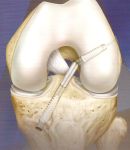

Artroskopie kolenního kloubu

- Náhrada PZV (předního zkříženého vazu) šlachou m. semidentdinosus a m. gracilis, BPB autoštěpem a BPB alloštěpem.

- Ošetření menisků kolenního kloubu (meniscectomie, sutura menisku)

- Ošetření defektu chrupavky (debridment, miktofraktury, Mozaikplastika, Trufit-syntetický štěp kolagen I a Beta Tricalcium phosphate)